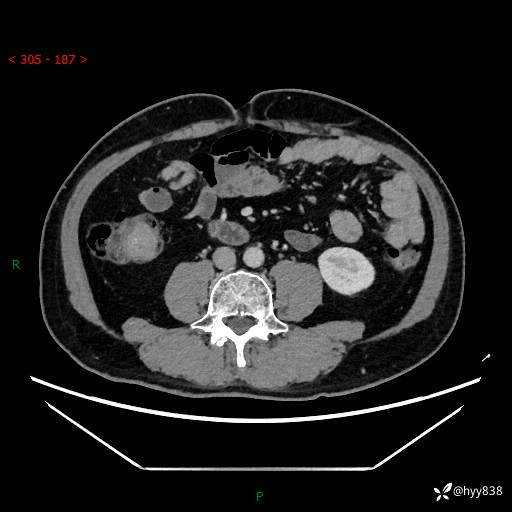

腹部CT增强扫描(外院CT平扫)

两期CT值:75hu 82hu